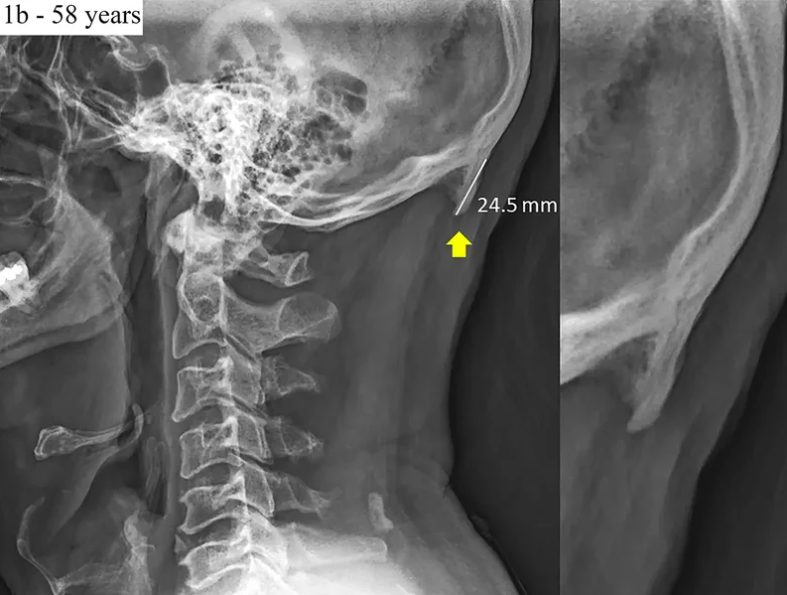

Hình ảnh được trích ra từ báo cáo đang khiến nhiều người bất ngờ.

Nhóm nghiên cứu theo đó cho biết người dùng thiết bị di động thường xuyên thường nghiêng đầu về phía trước để nhìn màn hình. Động tác này làm thay đổi trọng lượng của đầu từ phần cột sống đến các cơ phía say đầu khiến một phần xương phát triển thêm ở gân và dây chẳng. Phần xương này có cấu trúc như sừng và mọc ra từ đáy của hộp sọ.

“Phát hiện của chúng tôi làm dấy lên quan ngại về sức khoẻ hệ cơ xương khớp của người trẻ và nhấn mạnh nhu cầu can thiếp vào xu hướng này thông qua giáo dục cải thiện tư thế,” nhóm nghiên cứu nói trong báo cáo của mình. Được biết, để đưa ra được kết quả này, nhóm nghiên cứu đã xem xét 1.200 hình ảnh chụp X-ray tại Queensland với người tham gia khảo sát thuộc nhiều độ tuổi khác nhau.